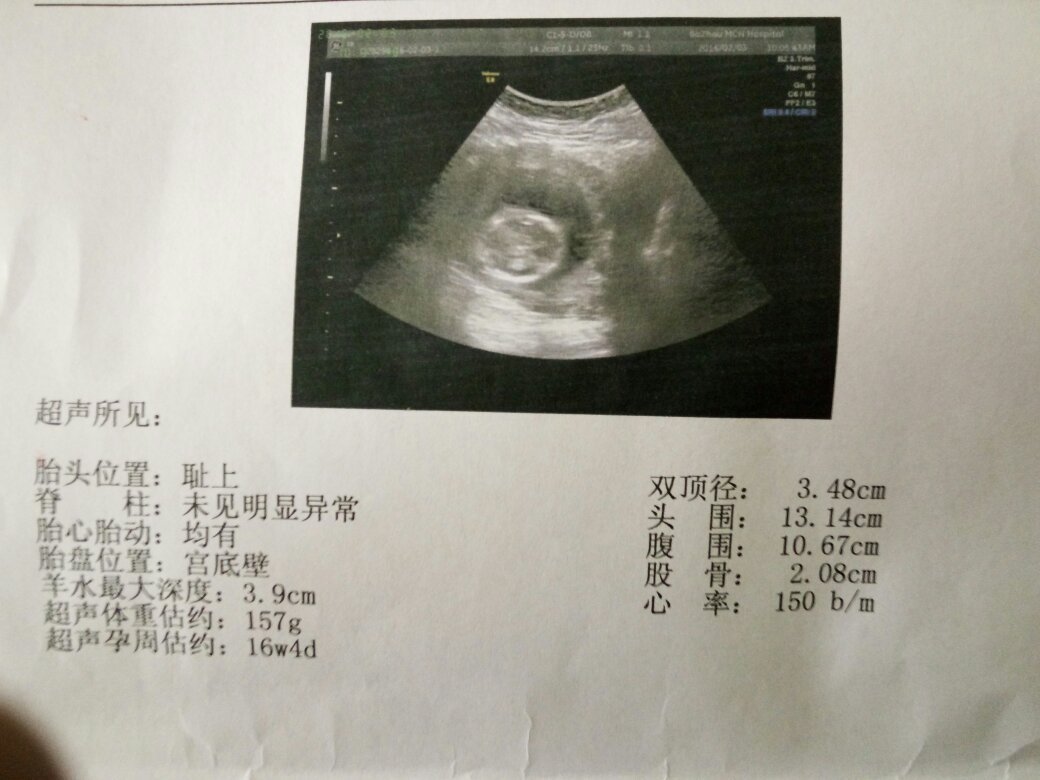

我老婆怀孕四个月了,去医院照b超,医生不告诉是男孩女孩,我们是新婚第一个孩子,求百度上的医生,帮我们看一下片子能看出男孩女孩吗求大神

1.7W+1D的BC数据: 胎囊 2.9*1.9 生的是男孩。 2.9W+4D的BC数据: 宫内见46.6*30.2mm孕囊双胞胎都是女孩今亲。 3.60天的BC数据: 孕囊大小是3.6* 1.6MM 生下的是男孩。 4.5W+6D数据:孕囊:25mm*11mm 则搂垃为男孩,胚囊:23*17*16则为女孩。 5.46天BC数据:孕囊:20*17*17 女孩。 6.7w+1D的BC结果:32*20mm妊娠囊女孩。 7.8周时是 1.6×1.7 生下的是千金。 8.62天葛栋凡:内见孕囊 2.6* 1.8 生的是可爱的男宝宝。 9.50天,孕囊35MM*27MM 生的是女宝宝。